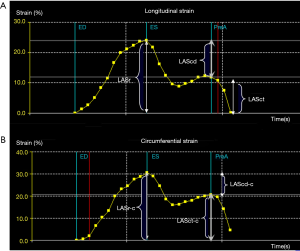

A semi-automated segmentation algorithm was used for volume calculation. The algorithm was initialized with 1 landmark located in the center of the mitral valve (MV) at the annulus level. The segmentation algorithm computes the deformation of the 3D model by solving a state estimation problem using an extended Kalman filter that combines the LA motion model, geometry, and edge detection algorithms. Strain was calculated based on changes in the lengths of different lines along each anatomical direction. To calculate longitudinal strain, 8 longitudinal lines (Figure 1A), each connecting 2 opposite LA basal points, were sampled from an automatically constructed triangular mesh. To calculate circumferential strain, 7 circumferential lines (Figure 1B) that were equidistantly distributed between the LA base and the LA apex were used. The strain time was then calculated for each frame s(t) = (L(t) – L(tr))/L(tr) x 100%, in which L(t) is the line length at time t and tr is the time of the left ventricular end diastole (ED). Global strain was calculated as the average strain of the respective directional lines of each direction.

Volume parameters were volume at onset of LA contraction (LA VpreA) and LAEF, while LAS parameters were longitudinal and circumferential strains. The reference point was set at the left ventricle ED. During the reservoir phase, the LA wall lengthened, so the strain in this phase had a positive value. In the other 2 phases, the LA wall shortened, so the strains in these phases had negative values. LA longitudinal strain parameters obtained using this technique included LA reservoir strain (LASr), LA conduit strain (LAScd), and LA contraction strain (LASct), and LA circumferential strain parameters obtained included LA reservoir circumferential strain (LASr-c), LA conduit circumferential strain (LAScd-c), and LA contraction circumferential strain (LASct-c).

The longitudinal strain during the reservoir phase (LASr) is the difference of the strain value at MV opening minus ventricular ED; the longitudinal strain during the conduit phase (LAScd) is the difference of the strain value at the onset of atrial contraction (PreA) minus MV opening; the longitudinal strain during the contraction phase (LASct) is the difference of the strain value at ventricular ED minus onset of atrial contraction; LASr-c is the difference of the strain value at MV opening minus ventricular ED; LAScd-c is the difference of the strain value at the onset of atrial contraction minus MV opening; LASct-c is the difference of the strain value at ventricular ED minus onset of atrial contraction; LA VpreA = Volume at onset of atrial contraction; LA EF = (Maximum atrial volume – Minimum atrial volume) / Maximum atrial volume.

There are 3 phases of normal LA activity: the reservoir, conduit, and contraction phases (17). The specific temporal activity of the LA and the corresponding strain curve are as follows: After ventricular ED, the LA fills and stretches, and its strain curve increases, reaching the peak at the ventricular end-systolic (ES) phase (i.e., before the MV opening); this phase is the reservoir period of the LA. After ES, the mitral valve opens, and the LA empties quickly until its pressure is equal to that of the left ventricle; this phase is the conduit period of the LA. Then, the strain decreases and the LA contracts, further expelling blood into the left ventricle, and the strain further decreases (18); this phase is the contraction period of the LA (Figure 6).

The 4D Auto LAQ tool was specially designed for the study of the LA. It can analyze longitudinal as well as circumferential LAS, and evaluate changes in strain parameters of LA activity in different phases (Figure 6). Due to the lack of a dedicated software for LAS measured by STE, software for LV analysis has also been applied in the study of LA pattern strains. The accuracy and repeatability of LAS measurements are affected by factors such as the thin-walled structure of the LA, irregular arrangement of LA myocytes (13), oval foramen on the atrial septum, and the 4 pulmonary vein openings on the LA wall among others.